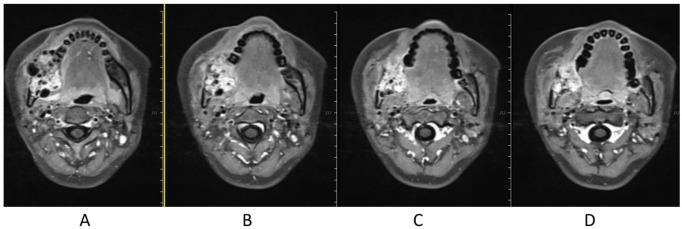

复发性成釉细胞瘤的碳离子放射治疗:一例报告

Carbon ion radiotherapy for recurrent ameloblastoma: A case report.

Ameloblastoma is a kind of benign, odontogenic tumor of epithelial origin, and surgery is mainstay treatment method; however, recurrence is common, and usually the treatment for recurrence is still surgery. We report on a patient of recurrent ameloblastoma treated with carbon ion radiation therapy and achieved a good efficacy. A 25-year-old female with relapse of an ameloblastoma was referred to the Wuwei Heavy Ion Center for carbon ion therapy. She had been initially diagnosed with ameloblastoma 8 years ago and underwent operation of right mandible ameloblastoma. After she transferred to our center, she accepted a dose of 60 GyE carbon ion radiation therapy, and the efficacy is good. Carbon ion radiation therapy can be an effective treatment option for ameloblastoma.

摘要

成釉细胞瘤是一种起源于上皮的良性牙源性肿瘤,手术是主要的治疗方法;然而,复发很常见,通常复发后的治疗仍然是手术。我们报告了一例接受碳离子放射治疗并取得良好疗效的复发性成釉细胞瘤患者。一名25岁复发性成釉细胞瘤女性患者被转诊至武威重离子中心接受碳离子治疗。她8年前最初被诊断为成釉细胞瘤,并接受了右下颌骨成釉细胞瘤手术。转至我们中心后,她接受了60GyE的碳离子放射治疗,疗效良好。碳离子放射治疗可以成为成釉细胞瘤的一种有效治疗选择。